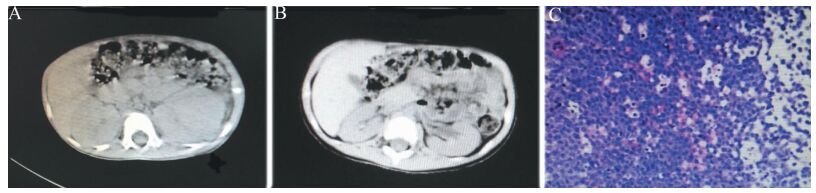

5例患儿入院时血红蛋白均低,血清乳酸脱氢酶(LDH)、尿酸、肌酐均偏高,2例出现蛋白尿,1例出现少尿[<250 ml/(m2·d)]。5例均行骨髓穿刺,经细胞形态学及免疫分型检查确诊NHL,见表 1、图 1。5例行彩色多普勒超声检查(彩超)均示双肾肿大,见图 1。

图 1 一例以AKI为首发症状的NHL患儿腹部CT及肾组织病理检查 A:治疗前腹部CT示双肾肿大;B:治疗后腹部CT示双肾体积恢复正常;C:肾组织病理检查示大量淋巴瘤细胞浸润(苏木素-伊红染色,×400) |

5例均采用中国儿童肿瘤协作组-B细胞NHL-2010化学治疗(CCCG-B-NHL2010)方案治疗[4]。根据国际淋巴瘤治疗反应标准进行疗效评估(但PET/CT未作为常规评价手段)[5]。5例经化学治疗后肾脏功能均恢复正常。治疗初期5例患儿均发生了急性TLS,其中实验室TLS 4例,经水化、碱化、利尿及别嘌呤醇口服治疗后缓解;临床TLS 1例,表现为心律失常,行血液透析等对症治疗后缓解。5例患儿的随访时间为13(6~24)个月,5例中2例于治疗早期发生黏膜炎,其中1例合并感染死亡,另1例治愈;5例中合并感染3例,均为肺部感染,1例放弃治疗,于院外因疾病进展死亡,另2例治愈。存活的3例患儿行彩超示肾脏结构正常,其中2例继续完成全部疗程,目前处于完全缓解中;1例在完全缓解后的治疗中出现骨髓复发,后因疾病进展死亡,见表 1。